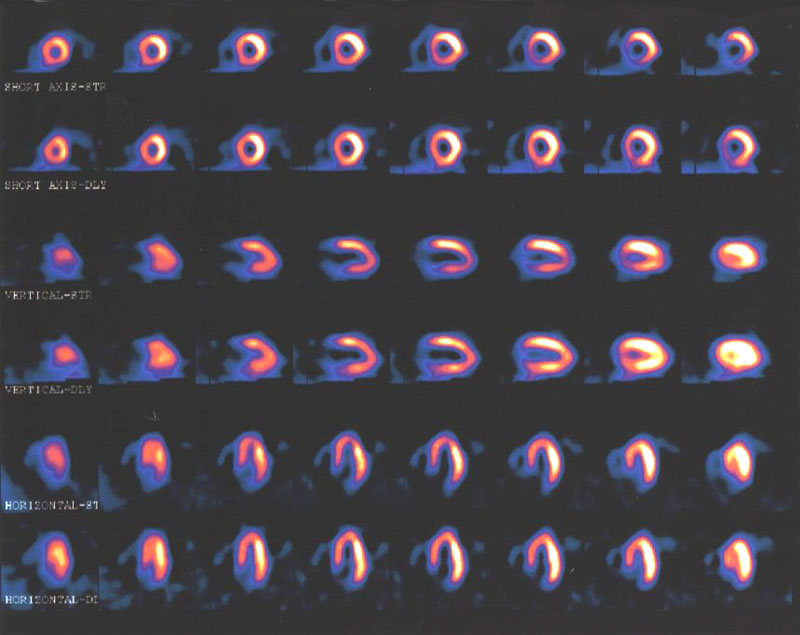

Alternativas menos invasivas para el diagnóstico de enfermedad coronaria

30 agosto 2016

En pacientes con sospecha de enfermedad coronaria, la evaluación con resonancia magnética o gammagrafía de perfusión miocárdica permite reducir las angiografías innecesarias. JAMA, 29 de agosto de 2016